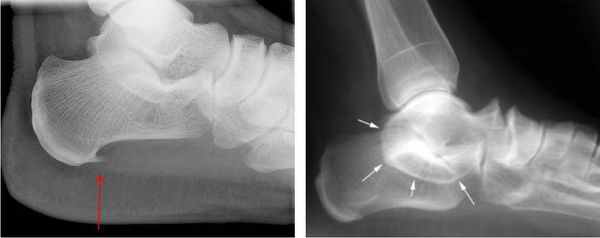

При подозрении травматической природы синдрома проводится рентгенография голеностопного сустава и стопы. Во время исследования также можно обнаружить костные выступы и остеофиты.

Для выявления патологий мягких тканей проводят МРТ голеностопного сустава стопы: могут быть обнаружены тендинит (дистрофия сухожилия), теносиновит (воспаление сухожилия), липомы или другие новообразования, варикозное расширение вен и кисты ганглиев.